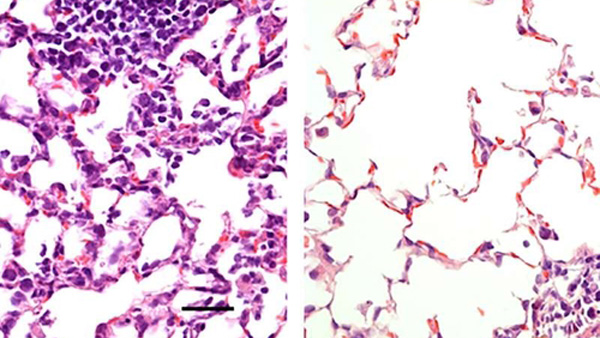

코로나19에 감염된 쥐의 폐. '코' 백신이 투여된 폐(右)와 투여되지 않은 폐(左)

미국 메디컬 익스프레스는 미국 워싱턴대 의대의 마이클 다이아몬드 분자 미생물학 교수 연구팀은 코를 통한 주입으로 면역반응을 유도할 수 있는 코로나19 백신을 개발해 쥐 실험에 성공했다고 보도했습니다.

이 백신은 독성을 제거한 감기 바이러스에 백신을 실어 콧속에 주입하는 것으로 단 한 번의 투여로 강력한 변역 반응을 유발할 수 있다고 연구팀은 밝혔습니다.